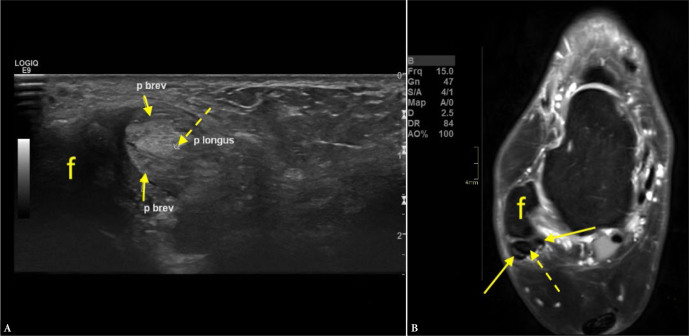

Aim: The purpose of this study was to evaluate the diagnostic value of ultrasound compared to magnetic resonance imaging (MRI) as a reference in detecting peroneus brevis split ruptures.

Material and methods: We re-reviewed 112 ultrasound examinations performed between 2020 and 2021 by three musculoskeletal radiologists with 8-10 years of experience. Patients were referred due to pain lasting at least 8 months in the posterolateral ankle. Ultrasound was performed using a LOGIQ E9 General Electric device with a 6-15 MHz or 18 MHz probe. Sixty-three patients who underwent MRI within 8 months and were included in the study. Ultrasound and MRI findings were categorized as: a) no peroneus split, b) presence of peroneus split, or c) unspecific findings. MRI served as the reference standard. Sensitivity, specificity, positive predictive value, negative predictive value, and accuracy were calculated.

Results: Seven cases (11.1%) were false positives (diagnosed on ultrasound but not MRI) and 9 (14.3%) were false negatives (missed by ultrasound but detected on MRI). Six cases (9.5%) were true positives (identified on both ultrasound and MRI), and 41 patients (65.1%) were true negatives (negative on both modalities). Ultrasound showed a sensitivity of 40.0% and specificity of 85.4%. The positive predictive value (PPV) was 46.2%, while the negative predictive value (NPV) was 82.0%.

Conclusions: Ultrasound demonstrated limited sensitivity but high specificity in detecting peroneus brevis split ruptures.